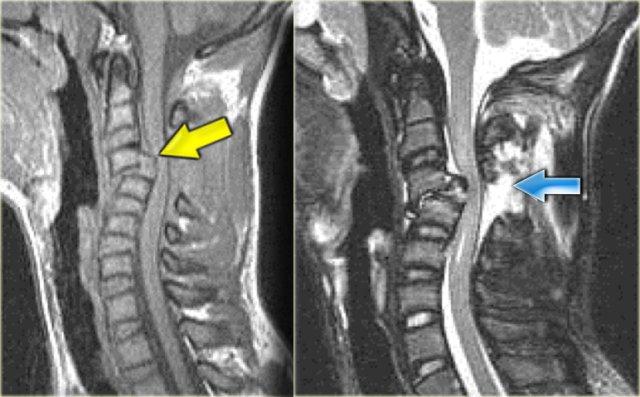

Hyperextension injury (3)

On the left two other examples of this hyperextension injury.

It is easy to find the injured disc, since it is the one with the high signal (arrows).

Notice the prevertebral soft tissue swelling in the case on the right.